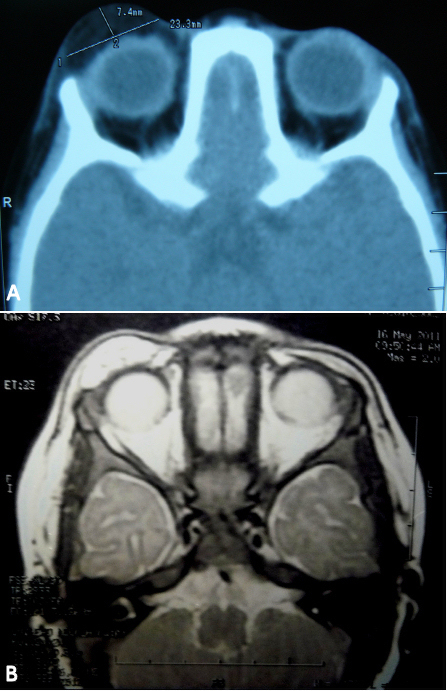

An 18-months-old male developed a tumor on his right upper eyelid over the course of two months. The tumor became significantly prominent, progressive enlargement over the last month. There was history of trauma to the area. On physical examination he was found to have a very large tumor, approximately 2×2 cm on the right upper eyelid, there appeared to be no discolorations, erythema, or signs of inflammation, it was a firm mass, and nontender to the palpation (Figure 1 [Fig. 1]). The remaining ocular examination was normal. The patient had no systemic manifestations. Orbital CT images demonstrated a large, well-circumscribed mass with a low density signal similar to intraorbital fat on the right upper eyelid. MRI presented a lesion with high signal intensity in T2-weighted images, and the lesion showed a well-marginated soft tissue mass with mixed signal intensity in T1-weighted images (Figure 2 [Fig. 2]). The superior visual field was compromised secondary to mechanical ptosis. The patient underwent an uncomplicated anterior orbitotomy through a superior eyelid crease incision and excision of the tumor (Figure 3 [Fig. 3]). The histological examination of the specimen revealed a lesion composed of mature adipose lobes separated by thick dense connective tissue tracts providing the diagnosis of a fibrolipoma (Figure 4 [Fig. 4]). At follow-up four years postoperatively the cosmetic appearance of the eyelid was very satisfactory and there had been no recurrence of the tumor.

Figure 2: CT images show a 7.4×23.3 mm-sized low density mass in the upper eyelid of the right orbit (A). T2-weighted magnetic resonance imaging (MRI) presenting a high signal intensity (B).